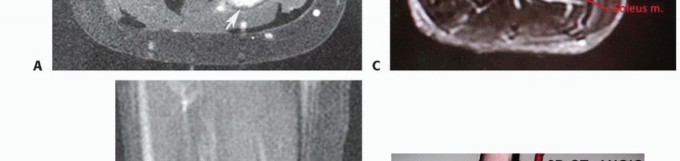

التصوير بالرنين المغناطيسي والتصوير المقطعي المحوسب

الفحص الدقيق لصور التصوير المقطعي المحوسب (CT) والتصوير بالرنين المغناطيسي (MRI) ضروري لتحديد قابلية الورم للاستئصال. تُظهر هذه الصور بوضوح حجم الورم وموقعه الدقيق، وتوغله في الأنسجة المحيطة.

- التصوير بالرنين المغناطيسي (MRI): يُعد الأداة الأكثر قيمة لتقييم أورام الأنسجة الرخوة. يوفر تفاصيل ممتازة للأنسجة الرخوة، مما يساعد على تحديد حدود الورم وعلاقته بالعضلات والأعصاب والأوعية الدموية. يمكنه أيضًا الكشف عن أي امتداد للورم إلى الفضاء المأبضي أو الأوعية المأبضية أو العصب الوركي.

- التصوير المقطعي المحوسب (CT): مفيد لتقييم مدى توغل الورم في العظام المحيطة (مثل الظنبوب والشظية) وللبحث عن أي انتشار للورم إلى الرئتين (النقائل).

يجب تقييم الفضاء المأبضي بعناية. غالبًا ما تمتد الأورام القريبة التي تنشأ داخل العضلة النعلية إلى الفضاء المأبضي وقد تشمل الأوعية المأبضية، العصب الوركي، أو كليهما. الأورام التي تمتد إلى وحول تشعب الأوعية المأبضية أو داخل عضلات الساق عادة ما تتطلب البتر، مما يؤكد أهمية التقييم الدقيق.